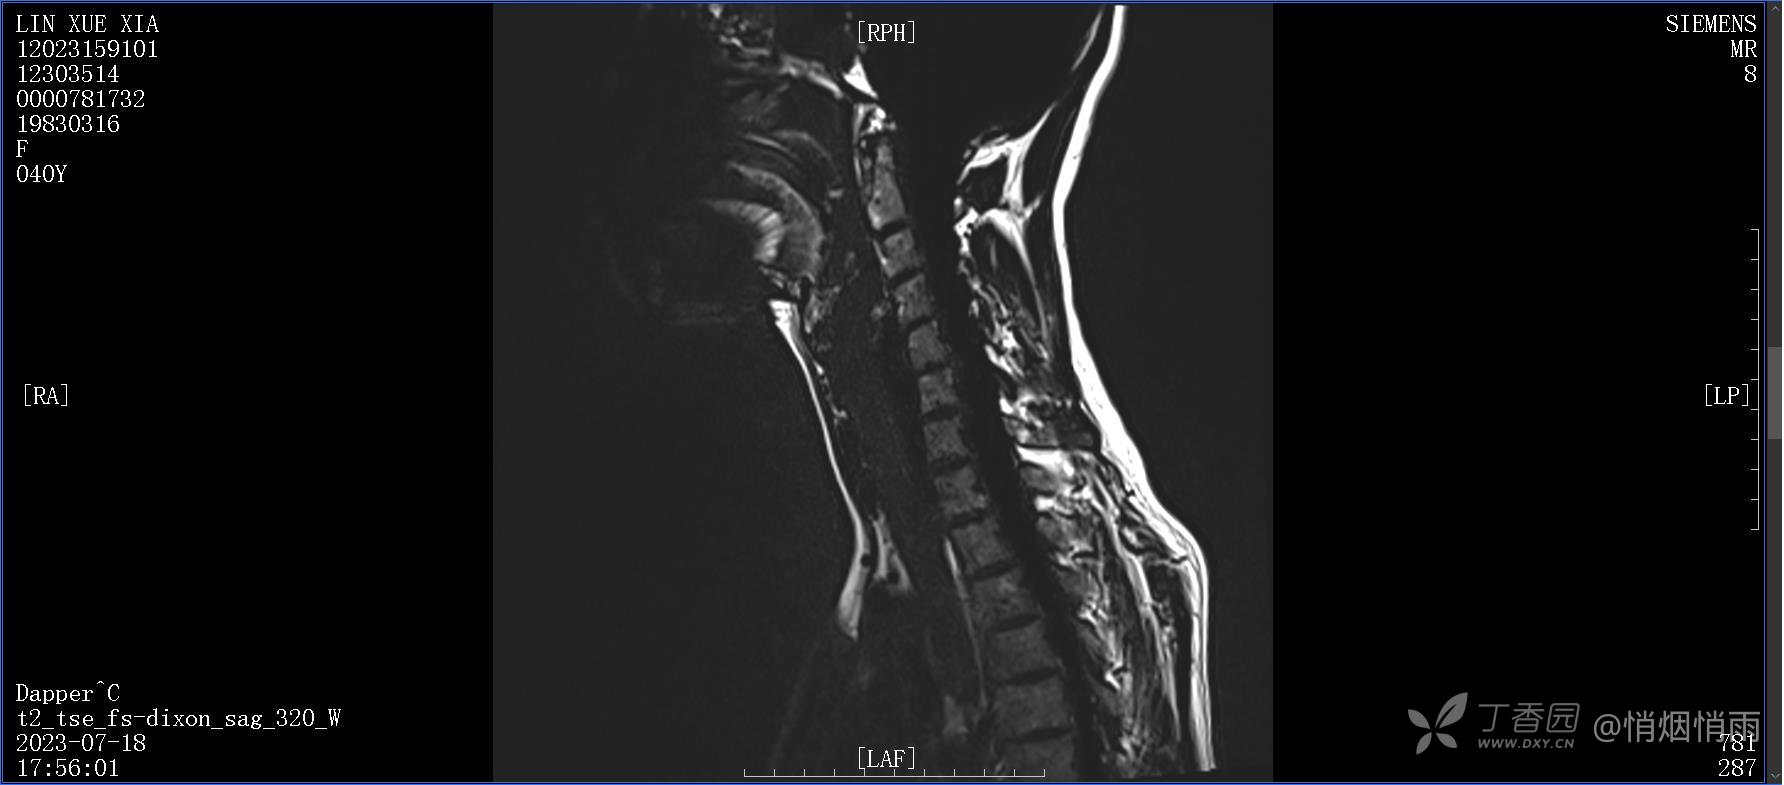

NeurothinkerZ 推荐患者女性,40岁,因右肩背部疼痛班活动受限4日余入院(2023-07-17)。

病史:入院前4天无明显诱因突然感右肩背疼痛伴随活动受限,自行口服依托考昔、艾瑞昔布等药物治疗,院外应用肩关节局部手法按摩等,均无明显改善。外院门诊诊为颈椎病。自诉既往多次“胸椎小关节紊乱”于当地诊所行手法按摩,治疗后好转,否认慢性疾病病史、外伤史、手术史,诉青霉素过敏,无其他药物食物过敏史,否认吸烟史、饮酒史,月经正常,经量正常。

查体:右肩关节局部轻度肿胀,肩胛区压痛明显,痛处不固定,肩关节痛性活动受限,jobe test(+),lift -off test(+),中指、环指感觉较余指减退,余肢端感觉及血运情况可。

目前的诊断,暂时依据辅助检查诊为肩袖损伤,但是患者疼痛的性质和特点,却不是单纯的肩袖损伤所致。考虑过胸廓出口综合征,但是该疾病会出现肩胛区的疼痛吗?(由于考虑到费用的问题,没再进行下一步的检查)带状疱疹会有如此的症状吗?